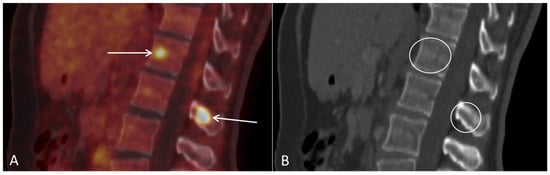

Figure 6. (A) Follow-up sagittal PET/CT fused and (B) sagittal CT after three series of chemotherapy shows metabolic activity in the spine suspicious for bone metastases ((A), arrows), with no corresponding lesions on CT ((B), circles).